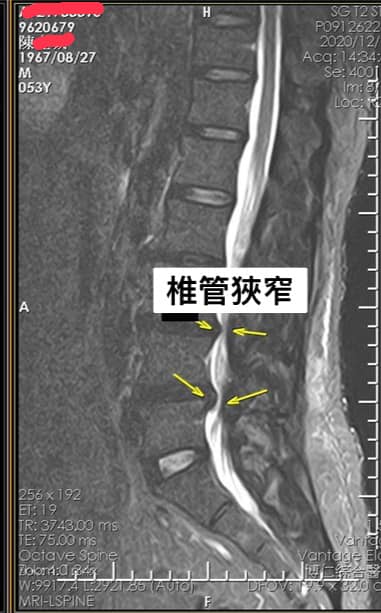

Cervical Spine Treatment Cases 腰椎治療案例 #巨大椎間盤突出一定要開刀嗎? #兩家醫學中心外科醫師說很嚴重! #有沒有辦法逆轉勝... 2021.08.10 ❖ 椎間盤突出治療醫案 ❖晨起痛爆整個人無法工作心情沮喪 😂骨科醫師說復健如果沒效可... 2022.05.12 #天才年輕賽車手巨大椎間盤突出醫案 #八周治療完全逆轉勝康復 #重新回到合法賽車場競... 2021.07.20 #腰椎滑脫痛苦不堪 #右腳麻痛無法彎腰刷牙 #感謝桃園市楊小姐熱情見證 #患者親自贈送... 2021.06.15 #巨大椎間盤突出醫案 #真的逆轉勝超感動 #三個月治療完全徹底改善 #脊刻救援成功 #徹... 2021.06.12 ⭕️L4L5巨大椎間盤突出治療醫案 🌟八週之內解除危機逆轉成功 😁順利降級成功解封印 💪... 2021.07.08 #腰椎多節椎管狹窄治療醫案 #腎臟病患者可接受中醫微創筋膜療嗎? #感謝台北市信義區張... 2021.06.01 #腰椎手術失敗綜合症候群 #感謝桃園呂伯伯熱情見證 #何時必須優先考慮再次動刀 #脊刻... 2021.07.31 #感謝新店吳先生熱情見證 #車禍後導致椎間盤突出醫案 #傳統復健六周無效痛苦不堪 #脊... 2021.05.29 #椎間盤突出治療醫案 #破紀錄三週解決 #真的逆轉勝 #感謝新莊周先生熱情見證 #脊椎整... 2021.05.26 #脊椎滑脫合併椎管狹窄醫案 #感謝台北市曹阿姨熱情見證 #之前大痛到無法走路只能拐杖... 2021.05.14 #嚴重椎管狹窄醫案導致寸步難行 #最嚴重走路無法超過十公尺 #疼痛到整個人憂鬱到不... 2021.05.07 #巨大椎間盤突出醫案逆轉勝 #感謝台北士林王先生熱情見證 #脊椎整合中醫微創療法 #原... 2021.04.29 #台灣越南國際醫療成功 #脊椎整合中醫微創療法逆轉勝 #腰椎椎間盤突出醫案 #曾經大痛... 2021.04.23 #椎間盤突出逆轉勝醫案 #原本骨科建議開刀 #脊刻救援成功 #感謝雲林患者陳小姐熱情見... 2021.04.09 ← 上一頁 7 8 9 10 11 下一頁 →